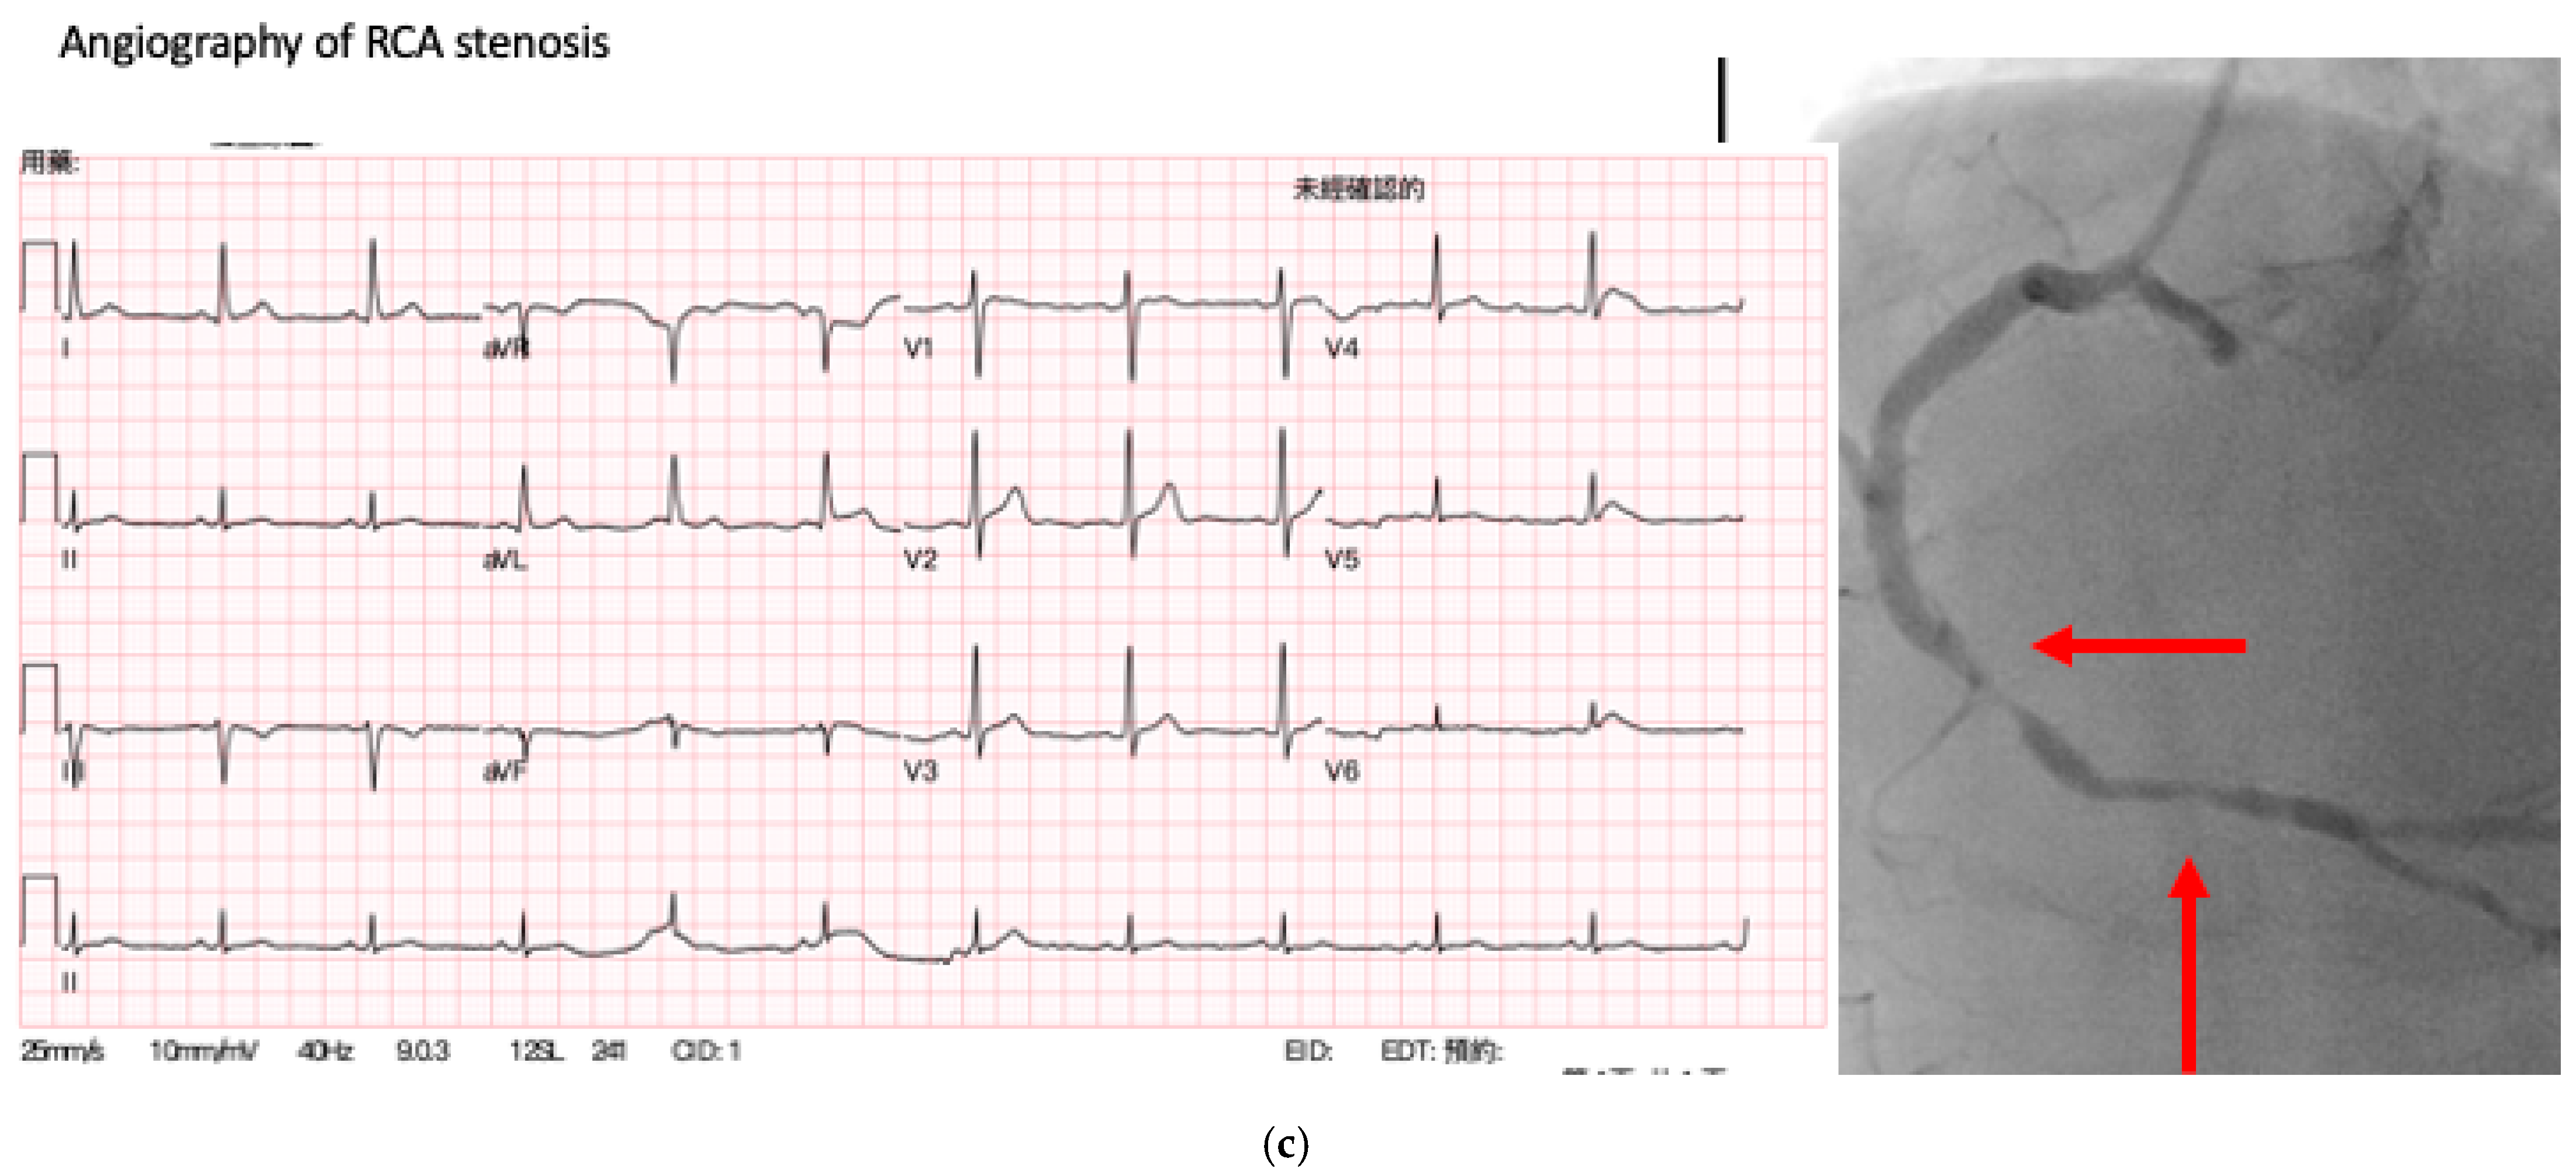

3.2. Detection of CAD and Prediction of the Obstructed Coronary Vessel

3.2.1. Random Selection Dataset

3.2.2. Subgroup Datasets